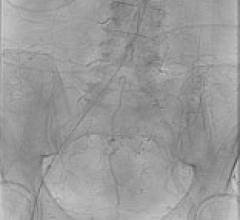

With a patient on the table, an interventional radiologist follows the movement of his catheter through a maze of arterial vessels. As he weaves his catheter through an intricate web of arteries to reach the coronary arteries and the area of interest, he gets constant real-time feedback from the monitors so he can carefully position the catheter to perform the intervention.